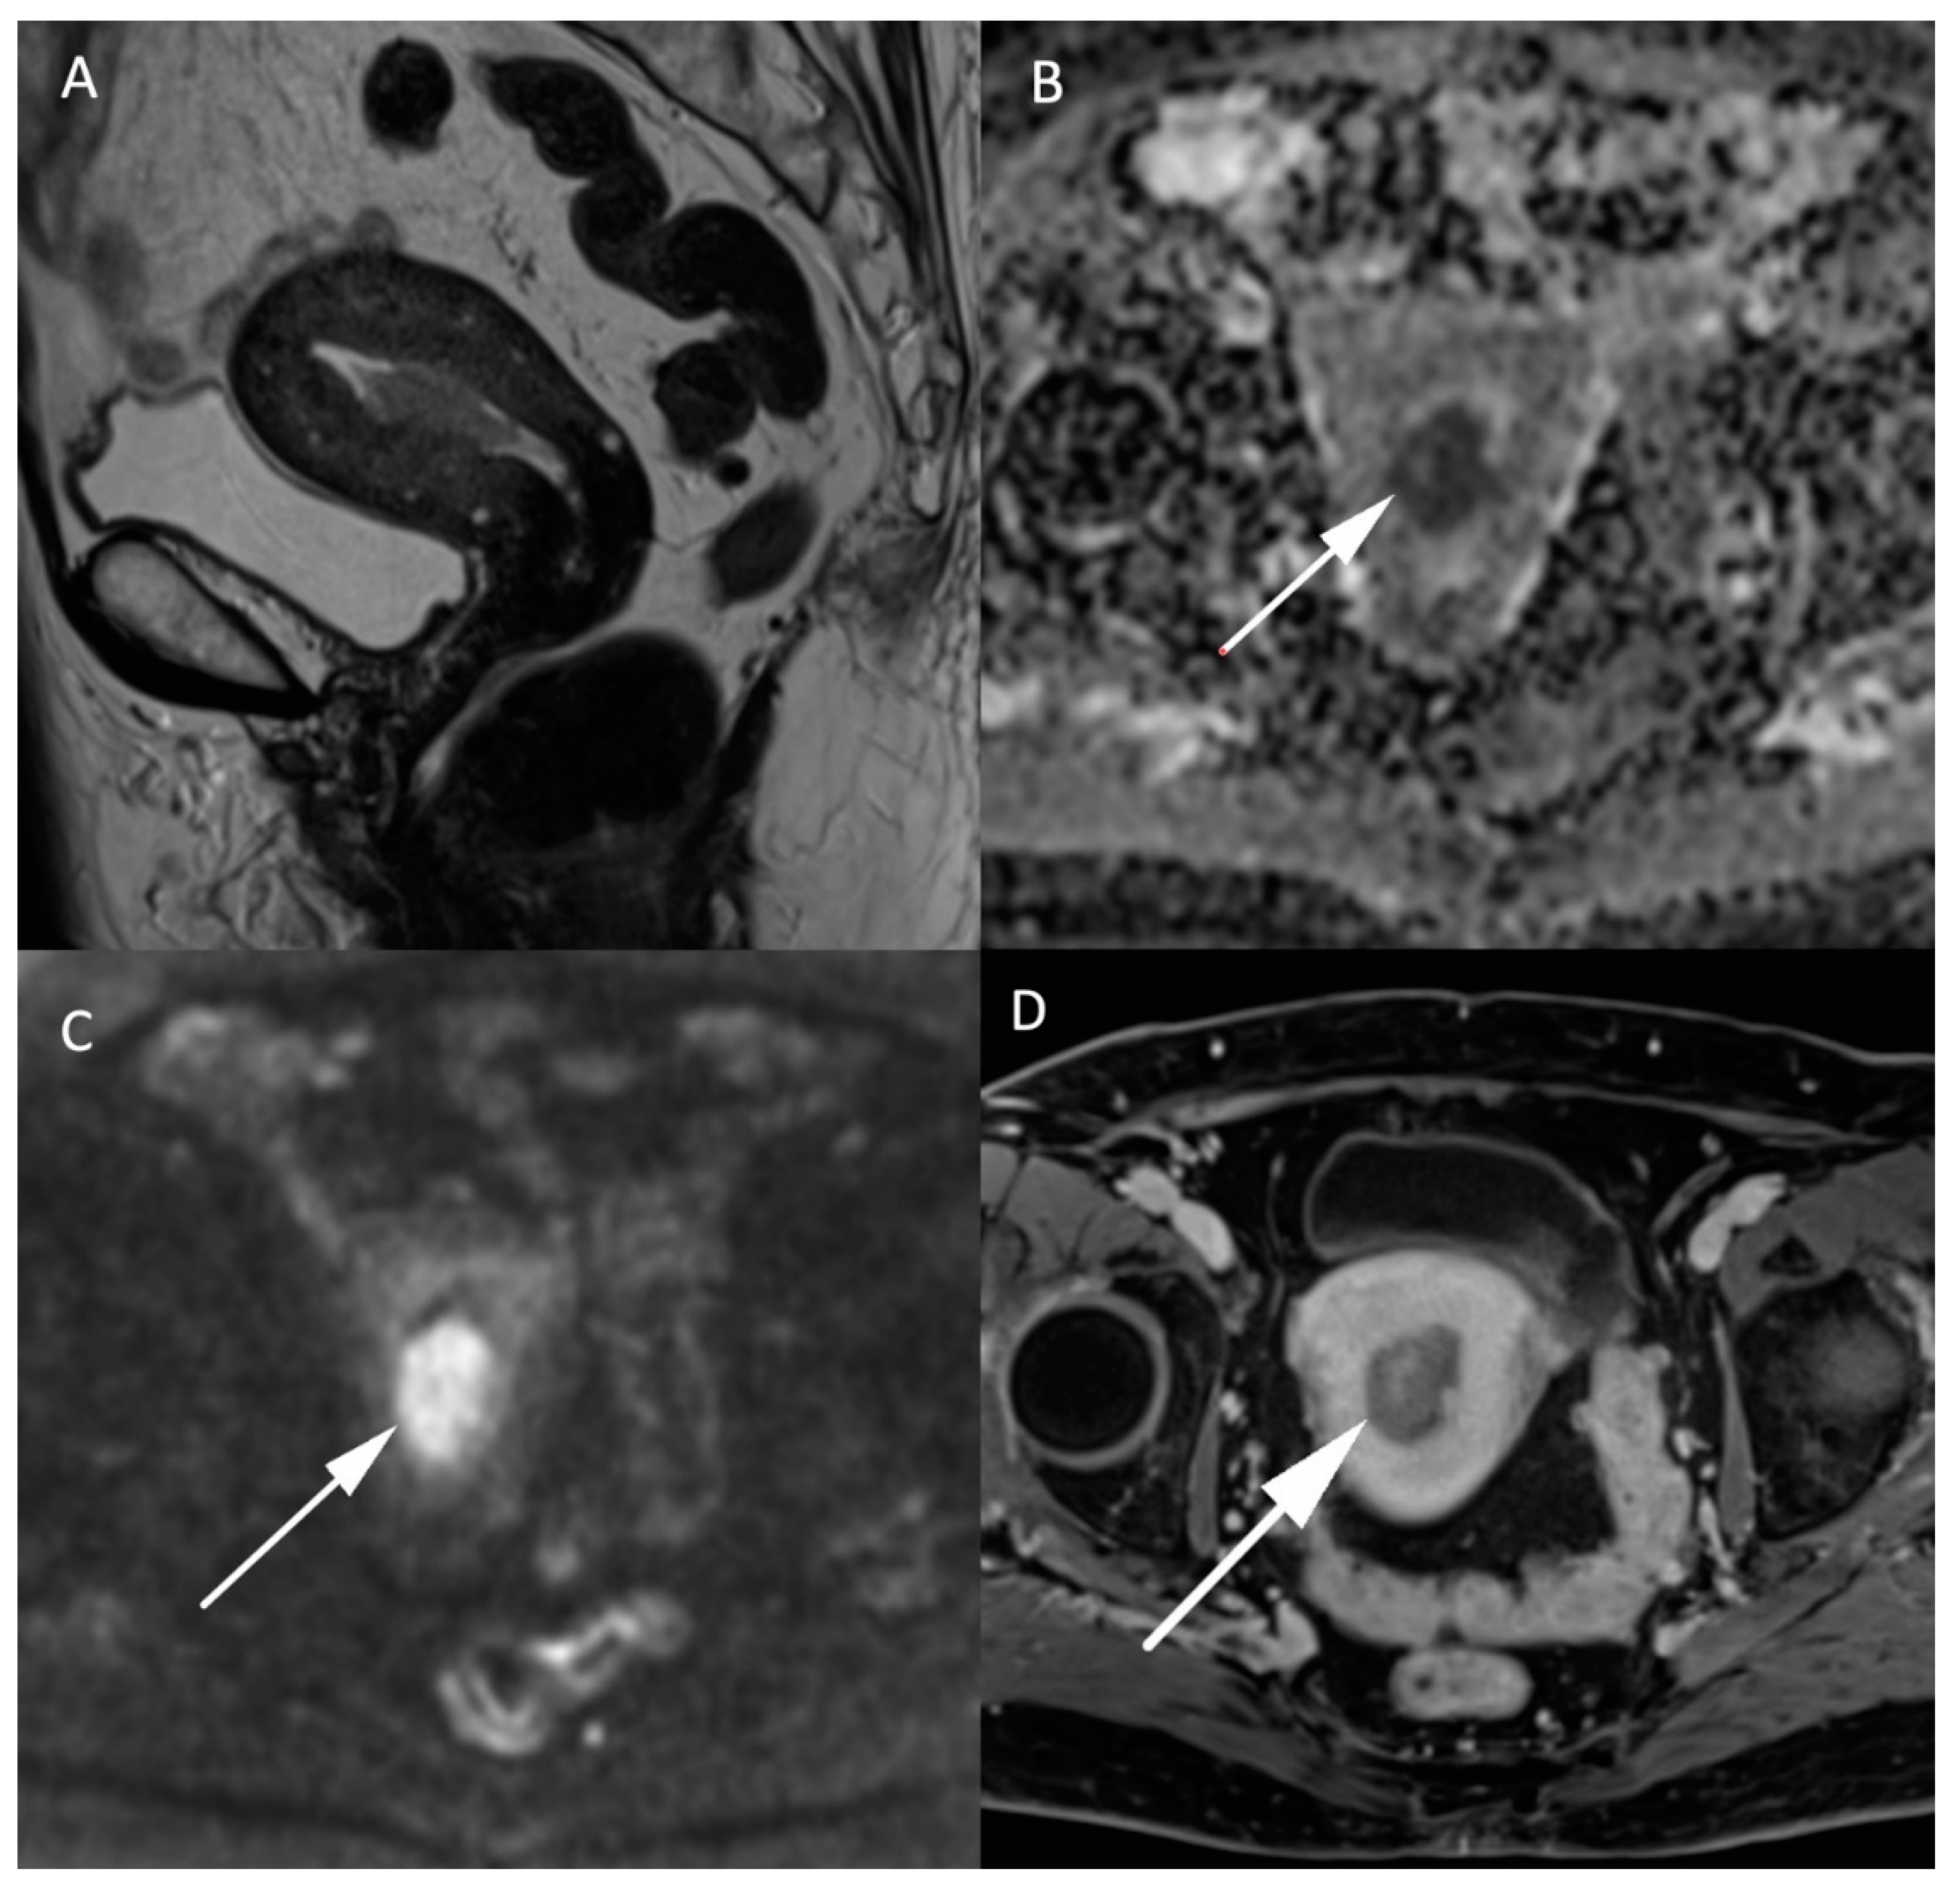

MRI in endometrial cancer is performed for the staging of the disease. Invasion of less than 50% of the myometrium to separate stage Ia and Ib is based on a morphologic T2W plane perpendicular to the endometrial cavity. Endometrial cancer is usually hyperintense to the myometrium but can be difficult to differentiate from the surrounding tissue as illustrated in Figure 3. On DWI cancer shows diffusion restriction with a high b-1000 signal and low ADC values compared to the normal endometrium and adjacent myometrium. The addition of DWI to T2W imaging significantly improves the staging of endometrial cancer [26,27]. It is even more indispensable in patients with impaired renal function who cannot benefit from gadolinium administration, and therefore, from contrast-enhanced MRI. However, the combination of DWI and contrast-enhanced MRI remains the best approach to predict myometrial invasion, as supported by a recent study on machine learning [28]. DWI is also helpful in detecting other pelvic depositions in high grade tumors [8]. A false positive high signal on DWI with low ADC values in the endometrial cavity corresponds to secretory and hyperplastic endometrium or blood during the female cycle which is easily recognized by its high signal on T1W FatSat sequences [8].

Figure 3.

MR images of an endometrial carcinoma in a 93-year-old woman. (A) Sagittal T2W image in the endometrial cavity with extension in the myometrium smaller than 50% of its thickness. (B) ADC map shows a restricted diffusion in the endometrial carcinoma visible as a “dark” area (arrow) in opposition with (C) high signal (arrow) on high b-value images (b = 1000 s/mm2). (D) post injection of gadolinium T1W image shows the endometrial carcinoma (arrow) with an enhancement less than the myometrium’s muscle.

Leiomyosarcomas are rare malignant tumors of the uterus and account for less than 10% of uterine cancers. The differentiation between benign leiomyoma and leiomyosarcoma is essential for the surgical management of these lesions. MRI and especially DWI play an important role in the characterization and management of both tumors. In addition to morphologic specificities of leiomyosarcoma, such as the intermediate T2 signal, nodular borders, hemorrhagic components, “T2 dark” areas and central unenhanced areas [29], DWI-based parameters constitute another essential tool to differentiate benign leiomyoma from leiomyosarcoma. As shown in Figure 4, uterine leiomyosarcoma usually shows low ADC values and increased signal intensity on high b-value DW images compared to the normal myometrium [15]. In the meta-analysis of Virarkar et al. which included 795 patients from eight studies, ADC values were significantly lower in leiomyosarcomas than in leiomyomas [30]. In a recent case-control retrospective study, Wahab et al. proposed a diagnostic algorithm to differentiate leiomyomas from uterine sarcomas based on the presence of lymphadenopathy, higher SI on high b-value images in the mass relative to the endometrium and ADC values inferior to 0.905 × 10−3 mm2/s [31]. The respective sensitivity and specificity of this algorithm to classify the uterine masses were 97% and 99% in a training set of 156 patients, 88% and 100% in a first validation set of 42 patients and 83% and 97% in a second validation set of 59 patients. Focally or globally reduced T2W SI and DWI-based SI lower than the endometrium allows to confidently diagnose the mass as benign [31]. However, this promising approach needs further validation by prospective multicentric studies.

Figure 4.

MR images of a leiomyosarcoma in a 54-year-old woman. (A) voluminous leiomyosarcoma with an intermediary T2W signal and irregular borders (arrow). Part of the leiomyosarcoma demonstrates a diffusion restriction with low (B) ADC values and high signal on the (C) b-1000 sequence. (D) post injection of gadolinium T1W sequence shows the absence of central enhancement consistent with central necrosis. All features are characteristic of malignancy within a leiomyoma.